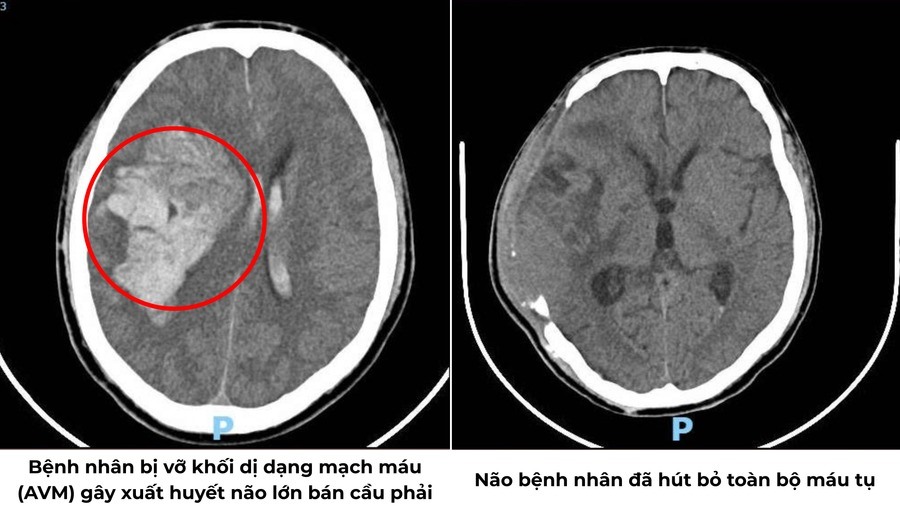

Chẩn đoán hình ảnh cho thấy bệnh nhân bị xuất huyết nội sọ lan tỏa do dị dạng thông động – tĩnh mạch (AVM) kích thước lớn, gây chèn ép nhu mô não và đẩy lệch đường giữa.

Trước tình huống này, quy trình báo động đỏ được kích hoạt. Trong 3 giờ phẫu thuật căng thẳng, các bác sĩ Khoa Ngoại Thần kinh đã mở sọ, cầm máu, lấy bỏ máu tụ giải phóng chèn ép.